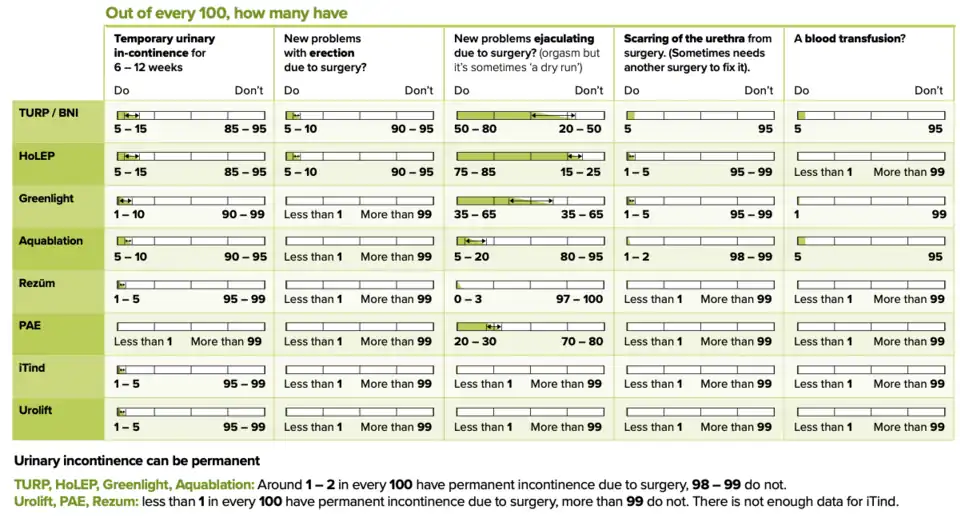

- ^ a b c d e f g "NHS England » Decision support tool: making a decision about enlarged prostate (BPE)". www.england.nhs.uk. Retrieved 8 September 2024.